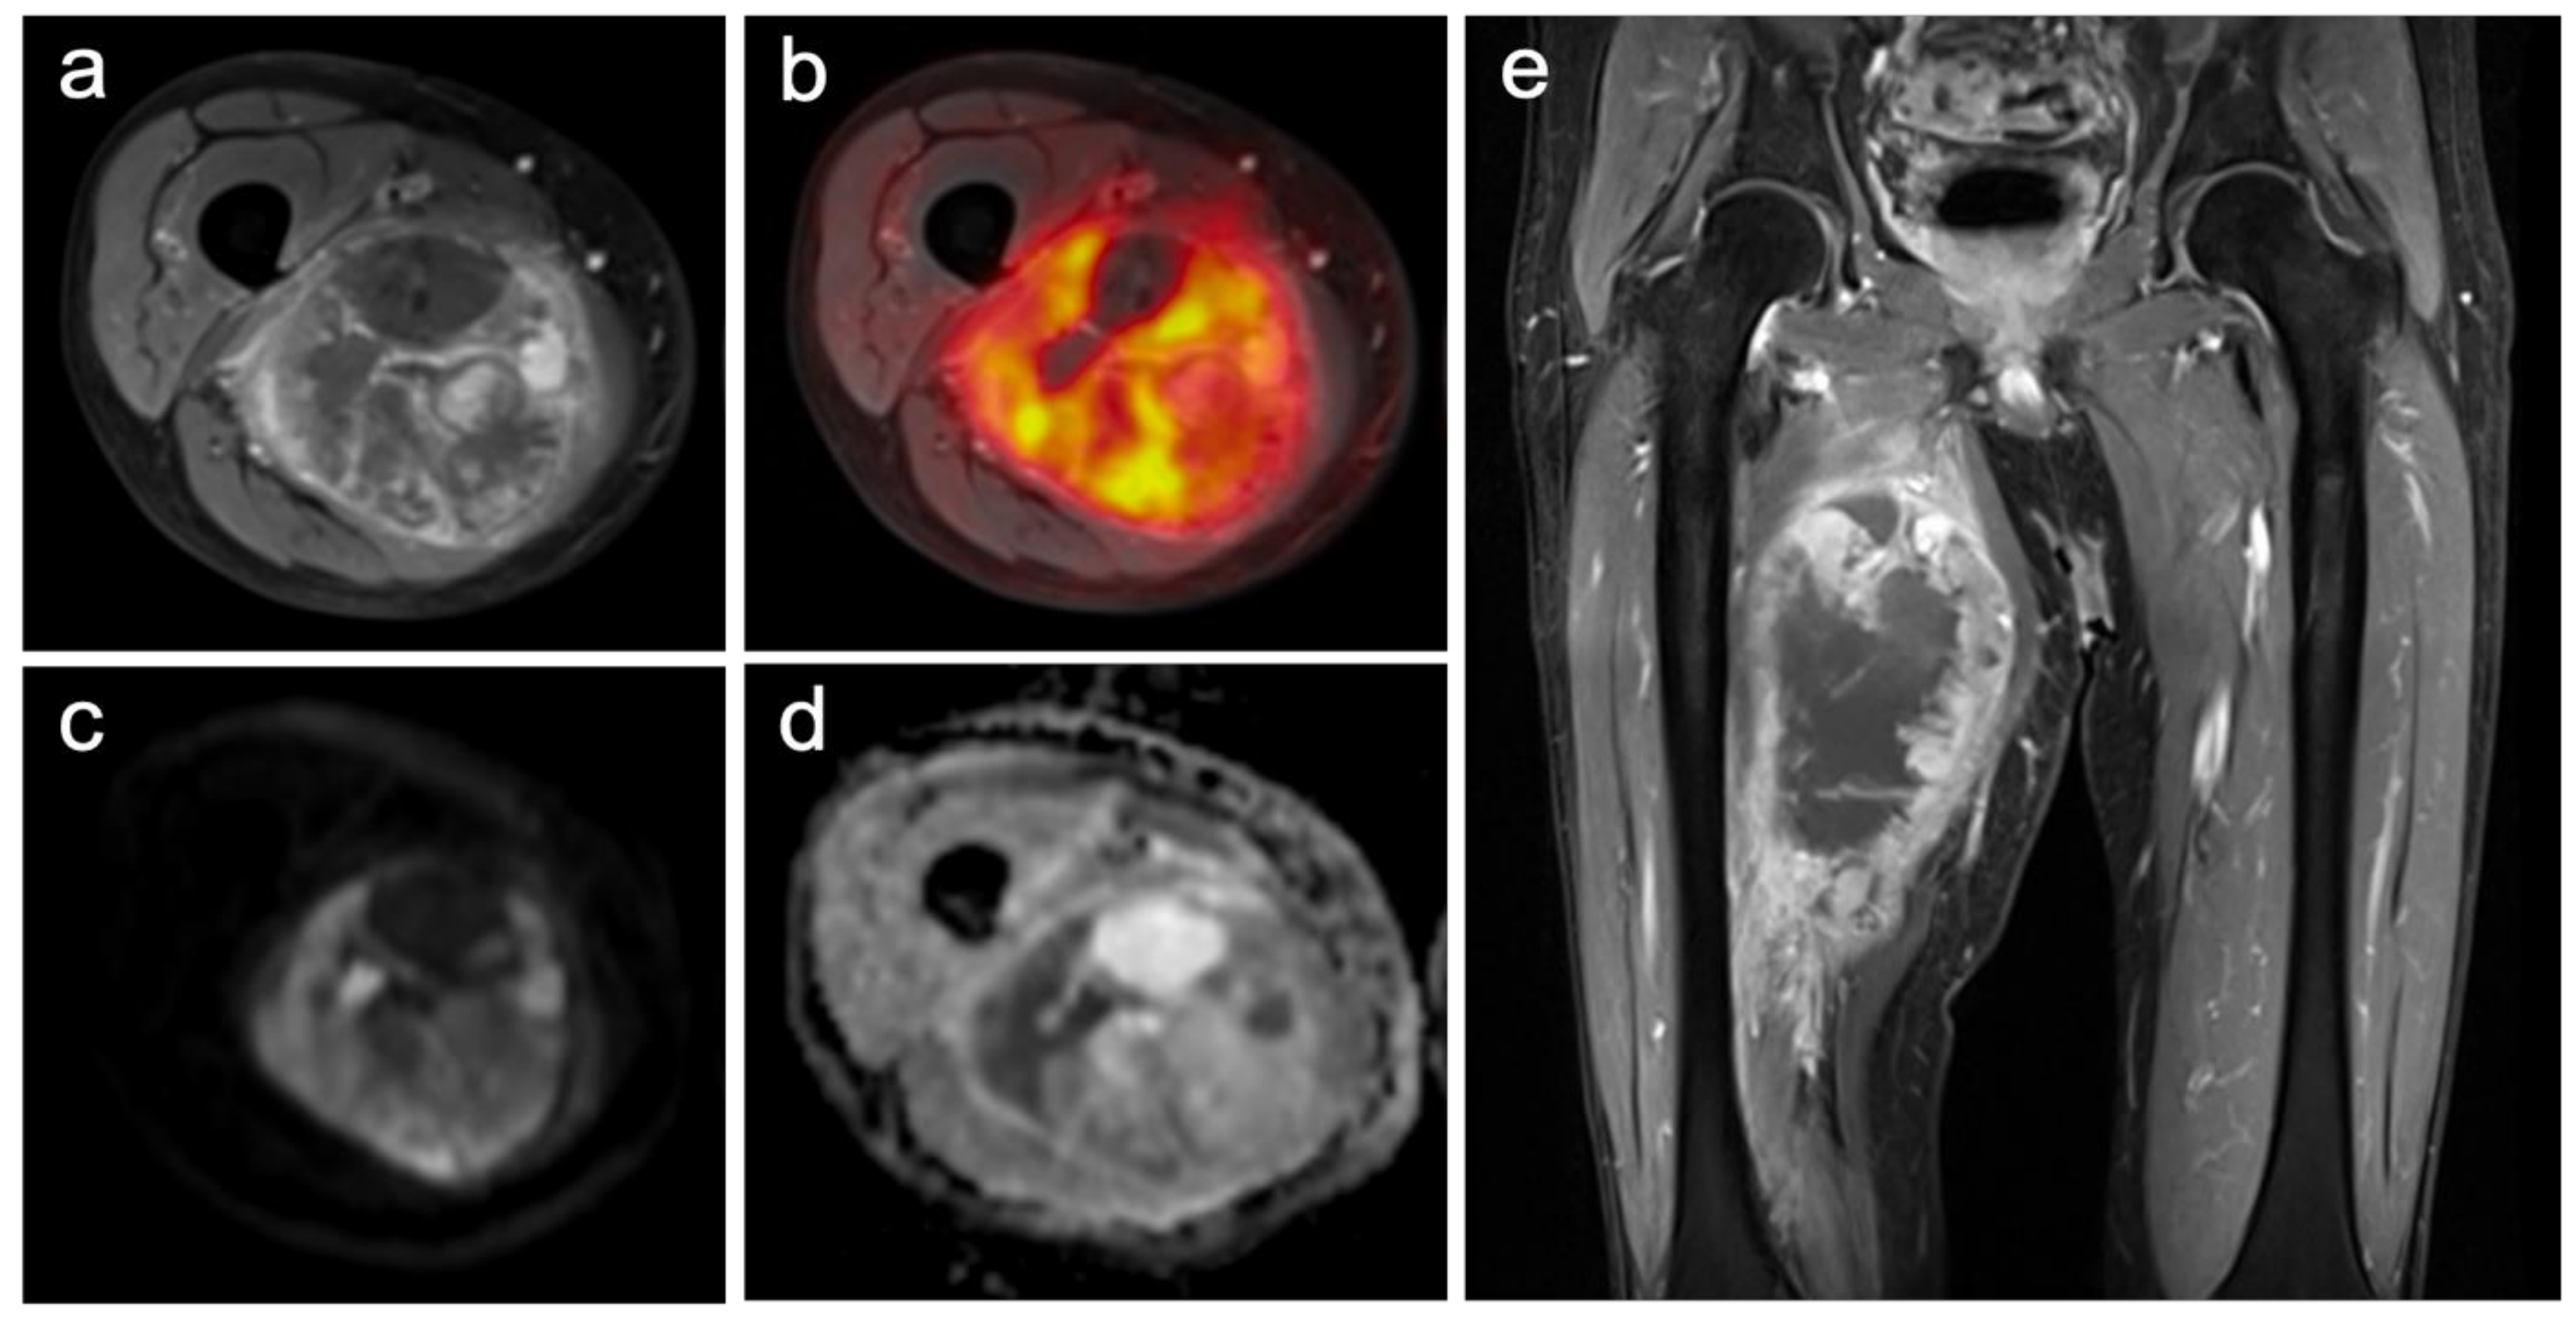

Figure 1.

Images of a primary soft-tissue sarcoma (undifferentiated pleomorphic sarcoma) of the right upper leg ((a) contrast-enhanced T1w TSE with fat-sat axial; (b) PET/MRI; (c) DWI b-1000; (d) ADC-map; (e) contrast-enhanced T1w TSE with fat-sat coronal). The large and partially necrotic tumor manifestation (23 mm) shows a pathologic glucose metabolism (SUVmax: 15.1; SUVmean: 7.5) and parts of restricted diffusion (ADCmean 1491; ADCmin 487). The reference standard revealed a grade 3 tumor with a good histopathological treatment response (regression grade 2), and metastatic spread could be identified.